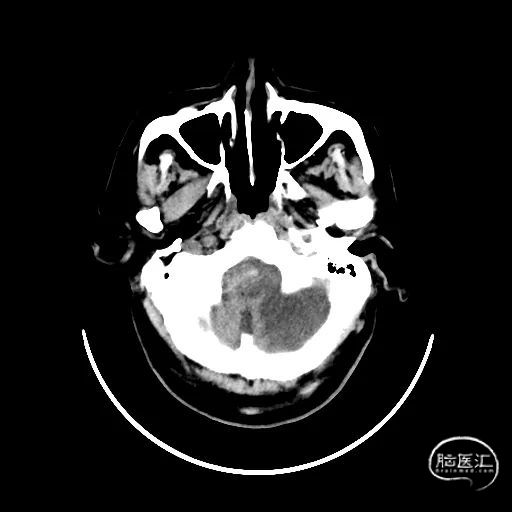

术后CT:未见明显脑出血,双侧小脑低密度影。

术后CTA:Bridge药物支架形态良好,前向血流良好。

术后9天MRI:

术后半年CTA:Bridge支架形态及贴壁良好,前向血流正常。